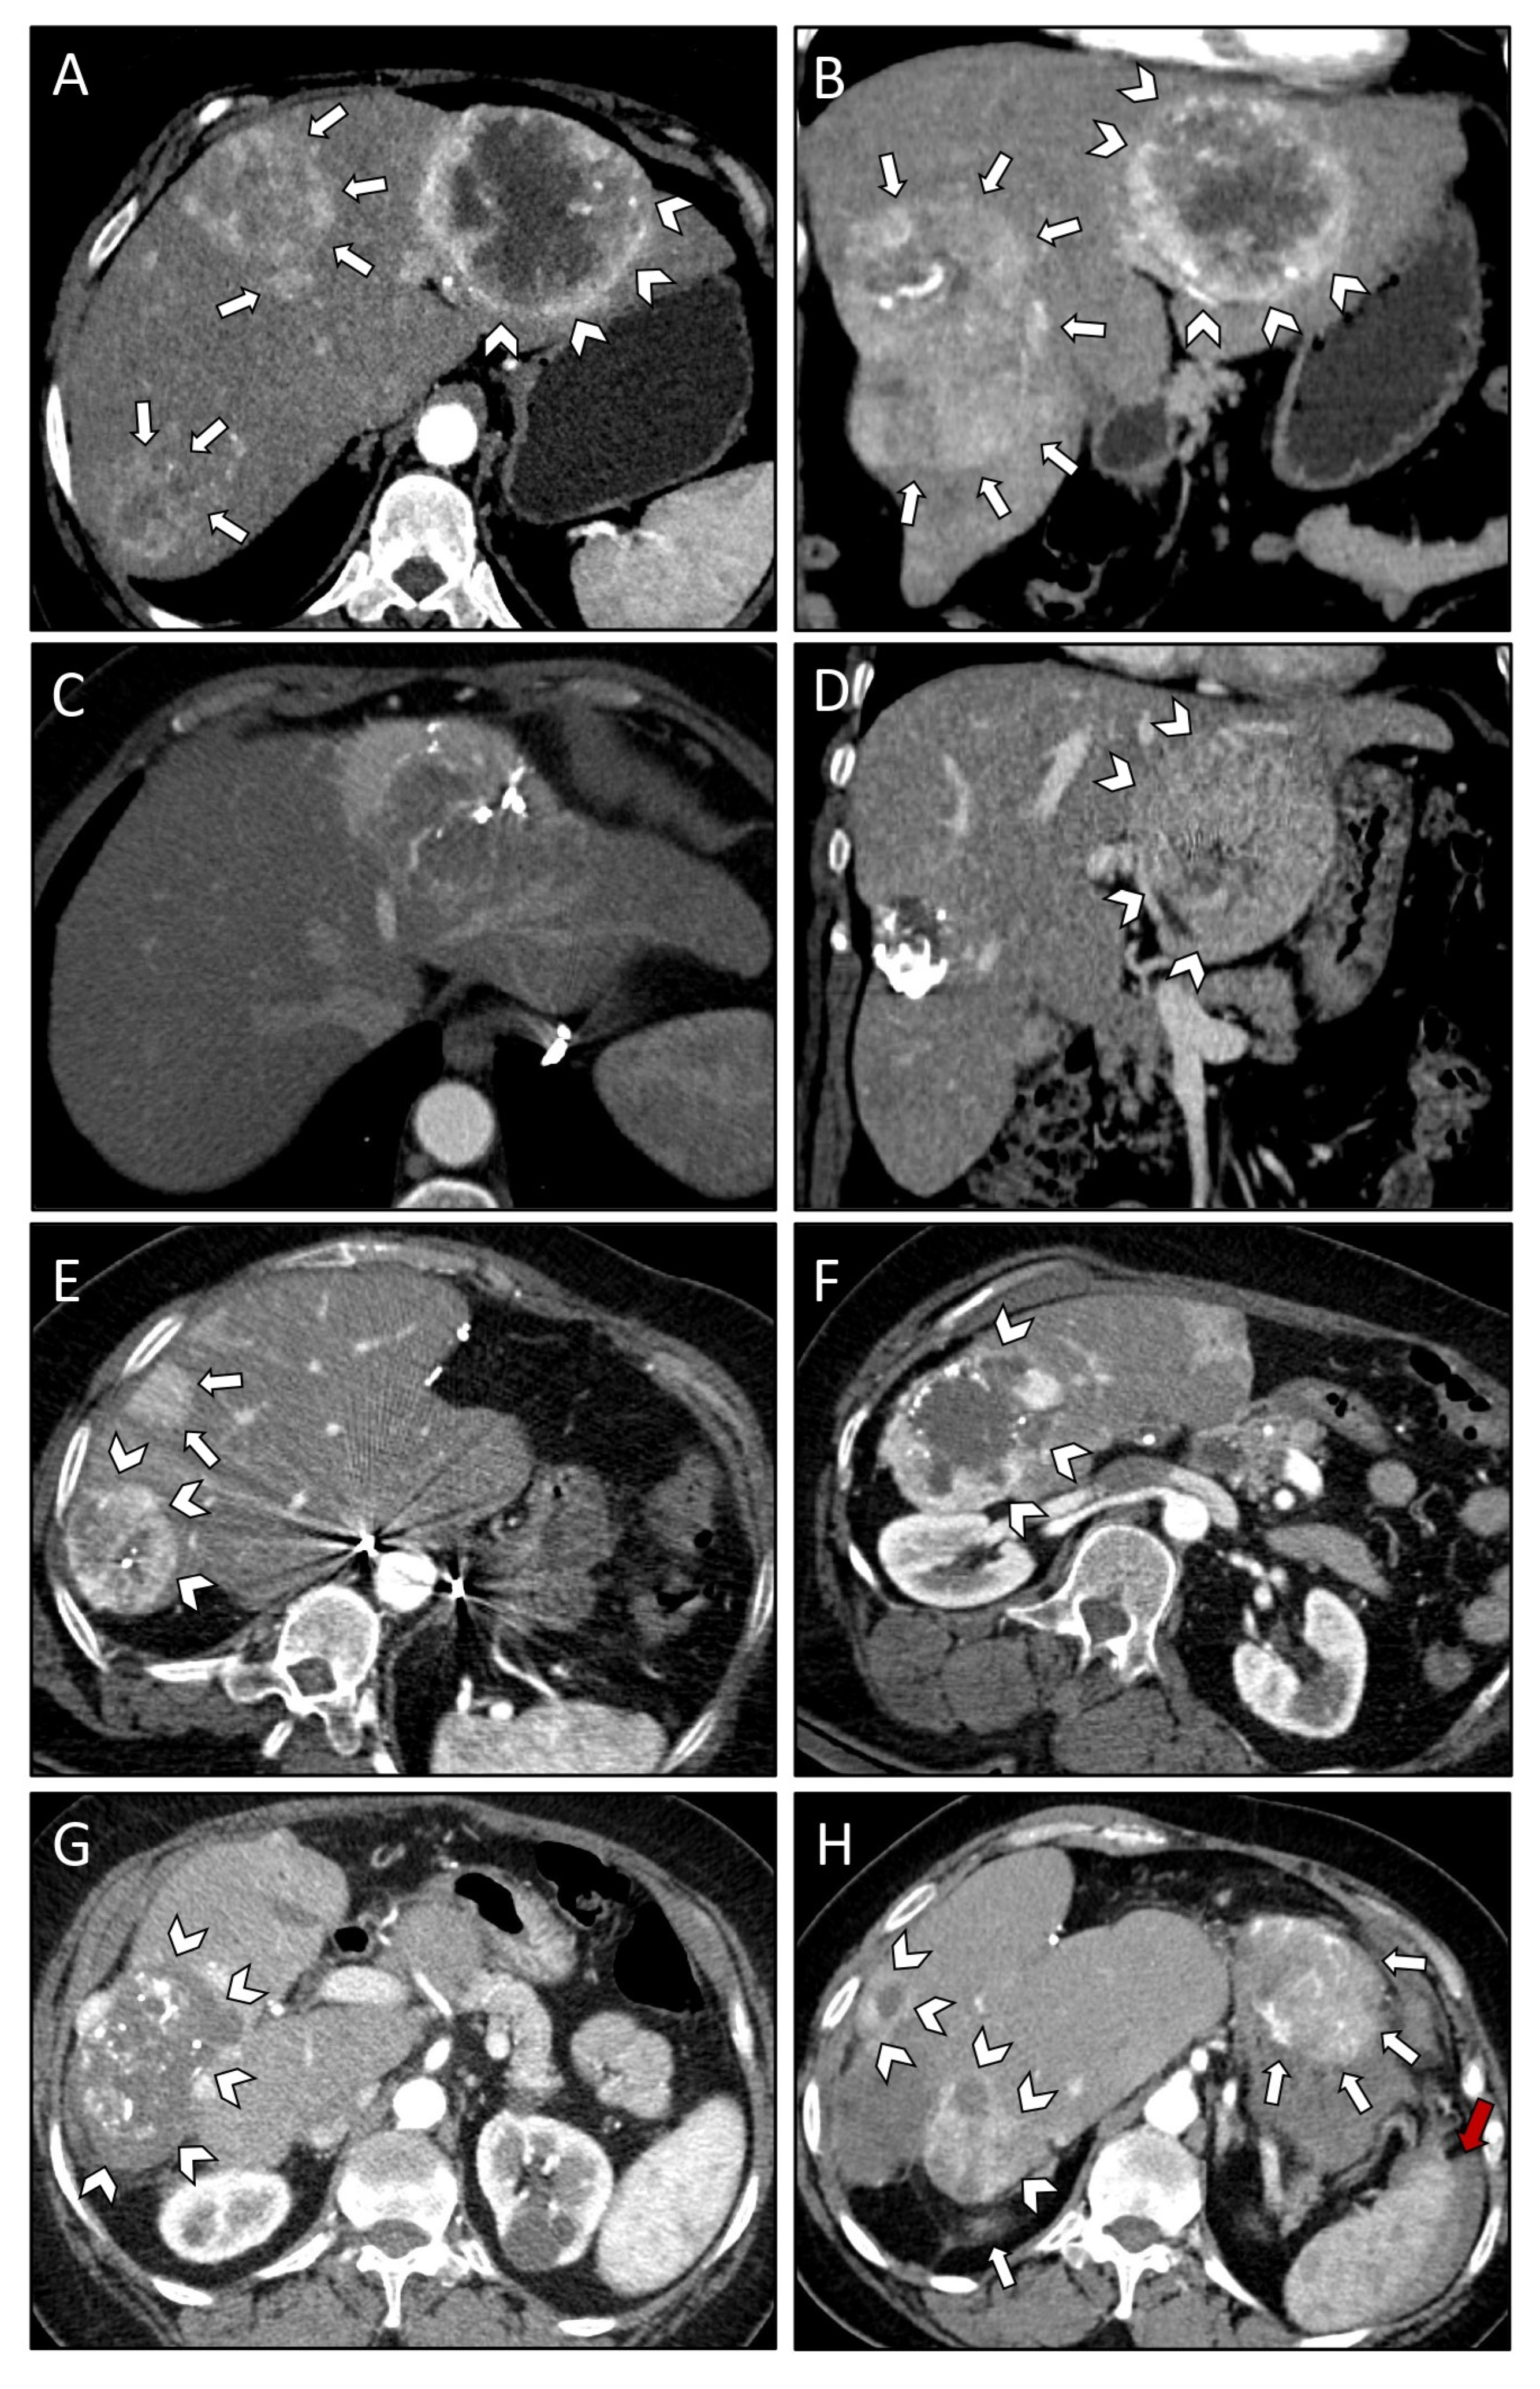

| Case Number | #1 | #2 | #3 |

|---|---|---|---|

| Patient age at diagnosis (years) | 67 | 39 | 65 |

| Patient sex | Female | Female | Female |

| Comorbidities/Notes | Parkinson’s disease | Childbed | Depression |

| WHO grade | II | II | II |

| Mitosis/10 HPF | 0 | 2 | 2 |

| Ki-67 index | 5% | 10–15% | 2% |

| Liver metastasis | |||

| Time to occurrence from initial diagnosis (years) | 8 | 8 | 15 |

| Location at initial diagnosis | Right lobe | Bilobar | Bilobar |

| Number at initial diagnosis | 1 | 3 | 3 |

| Size of largest metastasis at initial diagnosis | 13 cm | 12 cm | 13 cm |

| Paraneoplastic syndromes | Hypercalcemia | Hypoglycemia | None |